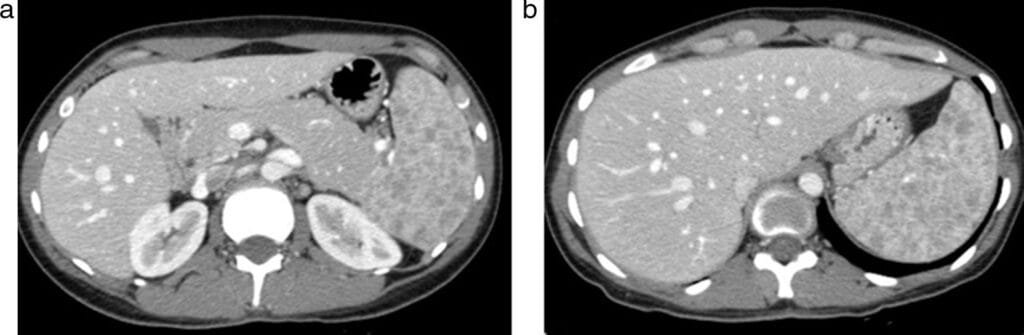

En términos generales, el tamaño del bazo inflamado suele ser mayor al doble del tamaño normal, aunque esto puede variar según la condición específica. El médico determinará el grado de agrandamiento mediante exámenes clínicos y pruebas complementarias como ecografías abdominales o tomografías computarizadas.

¿Cuál es la apariencia del bazo en una ecografía?

El bazo es un órgano que se encuentra en el abdomen, específicamente en la zona izquierda. En una ecografía, su apariencia puede variar dependiendo de diferentes factores como la edad del paciente y posibles patologías existentes. Sin embargo, generalmente el bazo se muestra como una estructura ovalada o ligeramente alargada.

Es importante destacar que la ecografía es una herramienta no invasiva y segura para evaluar el aspecto y tamaño del bazo. Durante el examen, se utiliza un transductor que emite ondas sonoras de alta frecuencia hacia el área abdominal, estas ondas rebotan en los tejidos internos y generan imágenes en tiempo real.

En la imagen ecográfica del bazo, se pueden observar distintas características importantes tales como:

- Tamaño: El tamaño normal del bazo varía según cada individuo pero suele tener aproximadamente entre 11 a 13 centímetros de longitud.

- Estructura: El parénquima o tejido interno del bazo aparece homogéneo y con una textura fina.

- Contornos: Los bordes del bazo deben ser lisos y regulares.

- Vasos sanguíneos: En algunos casos, también puede visualizarse el flujo sanguíneo dentro del órgano mediante Doppler color.

Es fundamental resaltar que cualquier alteración encontrada durante una ecografía debe ser interpretada por un médico especialista. La evaluación adecuada de las imágenes junto con otros datos clínicos permitirá diagnosticar posibles enfermedades relacionadas con el bazo. Por lo tanto, siempre es recomendable acudir a un profesional médico para obtener un diagnóstico preciso.